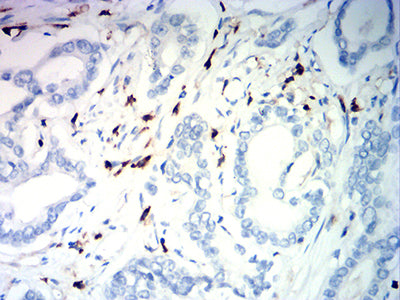

分类: 科研抗体货号: 32189别名: CR3A; MO1A; CD11B; MAC-1; MAC1A; SLEB6应用: IHC,FCM反应种属: Human